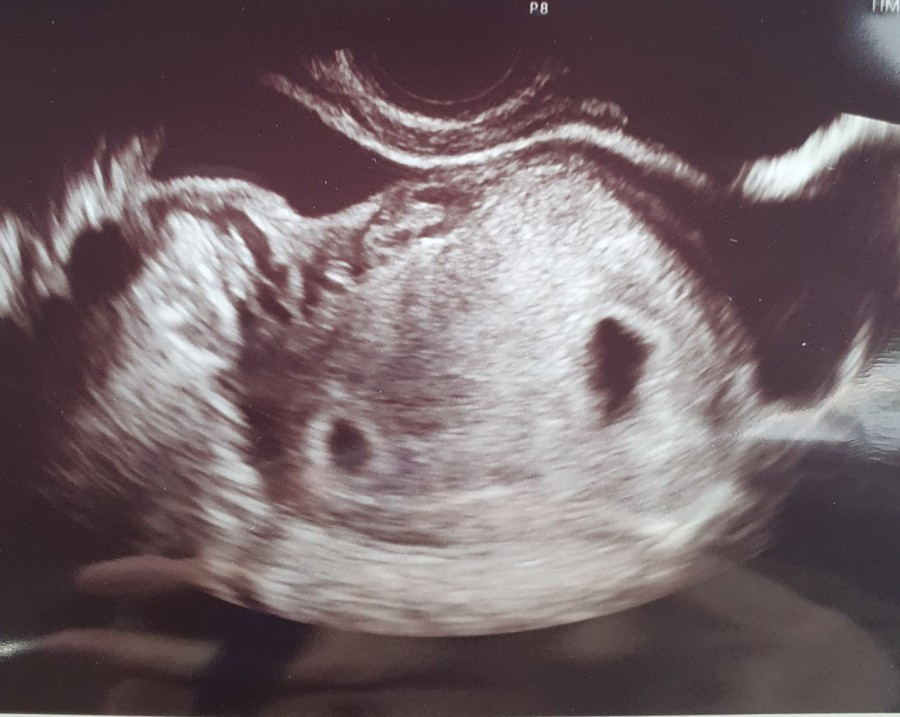

매일 같은 시간에 배에 직접 주사를 놓고, 아침저녁으로 항생제를 복용하면서 부작용과 싸워야 했다. 난자와 정자를 채취하고, 배아 이식을 마친 뒤 15일을 기다리는 시간이 길게 느껴졌다. 마음 한편엔 희망이 있었고, 그 희망은 기적처럼 쌍둥이 임신으로 이어졌다. 이제 모든 어려움이 끝났다고 생각했지만, 그건 진정한 시작에 불과했다.

임신 초기부터 자다가도 입덧을 한다거나, 갑자기 기절해 쓰러지기도 하고, 계속되는 하혈로 입퇴원을 반복했다. 안정기에 들어선 뒤에는 조산 위험까지 발견되어 자궁경부를 묶는 수술을 받아야 했다. 최선을 다해도 뜻대로 되지 않는 일이 반복되는 상황이 두려웠다. 7개월 동안은 밥 먹는 시간을 제외하곤 누워 지내야 했다. 갑작스럽게 찾아오는 호흡곤란과 수축으로 응급실을 오가며, 끊임없이 밀려오는 조산에 대한 공포가 나를 괴롭혔다. 두 아이가 여전히 연약한 내 몸 안에 있다는 사실이 매 순간 나를 불안하게 했다. 세상은 계속 돌아가고 있었지만, 나는 작은 방 안에서 매일 위기와 싸우며 아이들을 품었다. 무엇을 믿고 버텨야 할지 알 수 없던 그 시간들. 그 속에서 나름의 희망을 붙잡고 있었다.